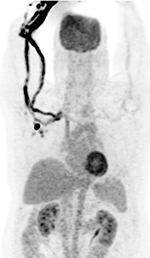

Figure 34 |

30 year-old woman with history of lymphoma. Axial CT, PET, PET-CT fused, and PET MIP images demonstrate intense FDG activity in the bilateral neck and paravertebral regions with a symmetrical distribution. Cross-sectional images clearly show that activity in the neck corresponds to fat and therefore consistent with brown fat activity. Brown fat activity is seen more commonly in younger patients and is also increased in response to hypothermia (so keep patients warm both pre and post injection of FDG). |